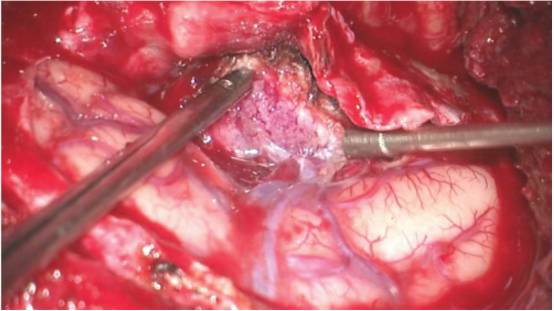

图10. 术者锐性切开硬膜,保护大脑,用双极电凝电凝硬脑膜边缘。如果肿瘤的硬脑膜尾超出骨窗缘,要扩大开颅,确保受累的硬脑膜完全暴露和切除。MR导航可以引导术者切除受累硬膜的过程。蝶眶脑膜瘤的硬膜内部分位于大脑外侧裂前部。

沿着硬膜内肿瘤的基底离断血供。沿肿瘤周边的脑组织环形分离,在肿瘤周边放置棉片并将减压后的肿瘤边缘向脑组织的方向牵拉。

此时,识别和保护大脑中动脉远端分支(M3、M4)是重要的。这些沿大脑中动脉主干发出的分支,可能包裹在肿瘤内,但通常有完整的蛛网膜分离界面,而动脉壁没有受累。

一旦肿瘤完全分离和切除,任何残余的肿瘤结节或浸润的硬脑膜也应一并切除。但在眶上裂和海绵窦水平受累的硬脑膜应完好保留。